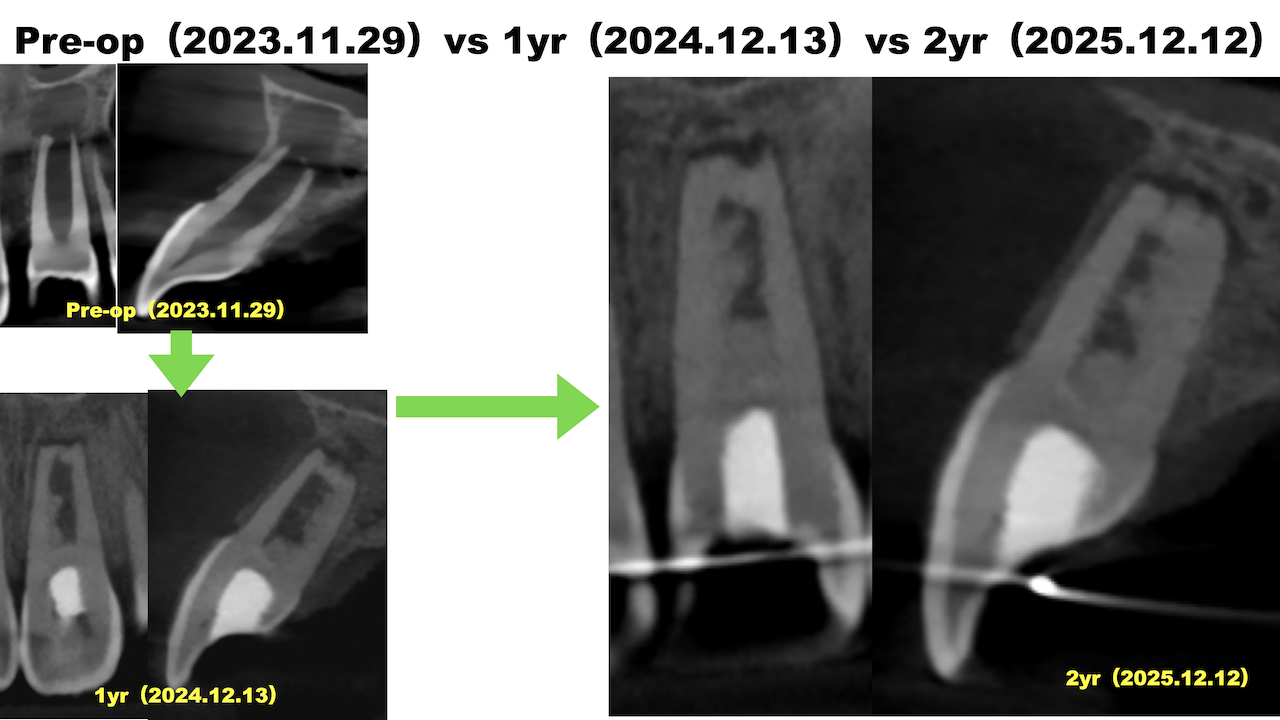

初診時、1年経過観察時と比較した。

大きく問題が解決している。

次回はさらに1年後の3yr recallである。

またご報告したい。